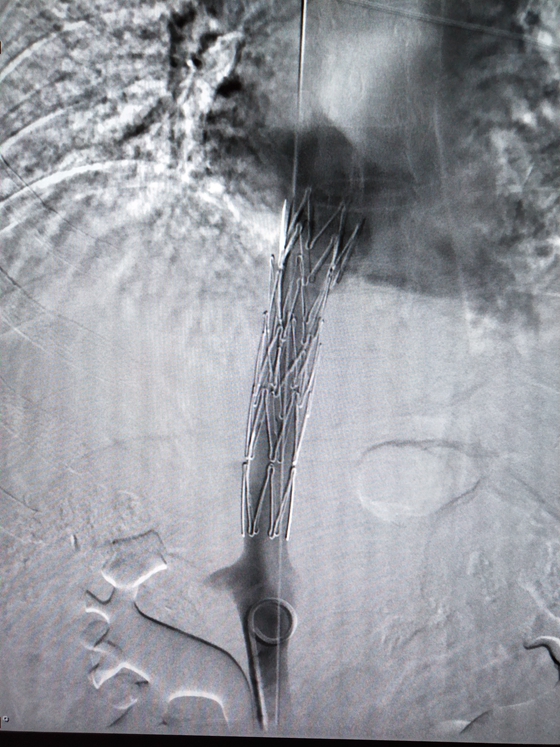

球囊扩张

3月25日,在放射介入科主任胡康新教授的指导下,汤金城医师、李毅副主任医师和黄彬副主任医师为患者实施介入治疗。手术在DSA引导下,医生先经股静脉置管进行造影,明确诊断并确定了病变类型,观察下腔静脉的狭窄程度和梗阻远端有无血栓以及肝静脉是否通畅。随后从右颈静脉插入另一导管,经上腔静脉和右心房导入下腔静脉上端,两根导管同时注入造影剂,以便更清楚的了解病变长度。在明确了病情后,医生再经导丝插入球囊扩展导管置狭窄处,经反复扩张后,直至球囊完全张开。扩张后,植入内径合适的“Z”形支架。手术仅历时一个半小时,手术顺利完成,病人安返病房。